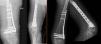

En 2 pacientes con fracturas diafisarias con un canal demasiado estrecho para realizar un enclavado se eligió para su tratamiento una placa con tornillo deslizante de cadera. En uno de ellos, un fémur muy plano y delgado no permitió el uso de placa con tornillo deslizante de cadera ni de clavo largo, debiendo usar una placa de bloqueo estándar de 3,5 (fig. 3).

Fractura diafisaria de la tibia (AO/OTA 42)De los 5 pacientes que presentaron una fractura diafisaria de la tibia, en 3 de ellos se realizó un enclavado, sin incidencias intraoperatorias. En los otros 2, el problema principal fue un hueso de canal estrecho y deformado por fracturas previas, que obligó al uso de un fijador externo monolateral en un paciente y una placa de tibia proximal preconformada en el otro (fig. 5).